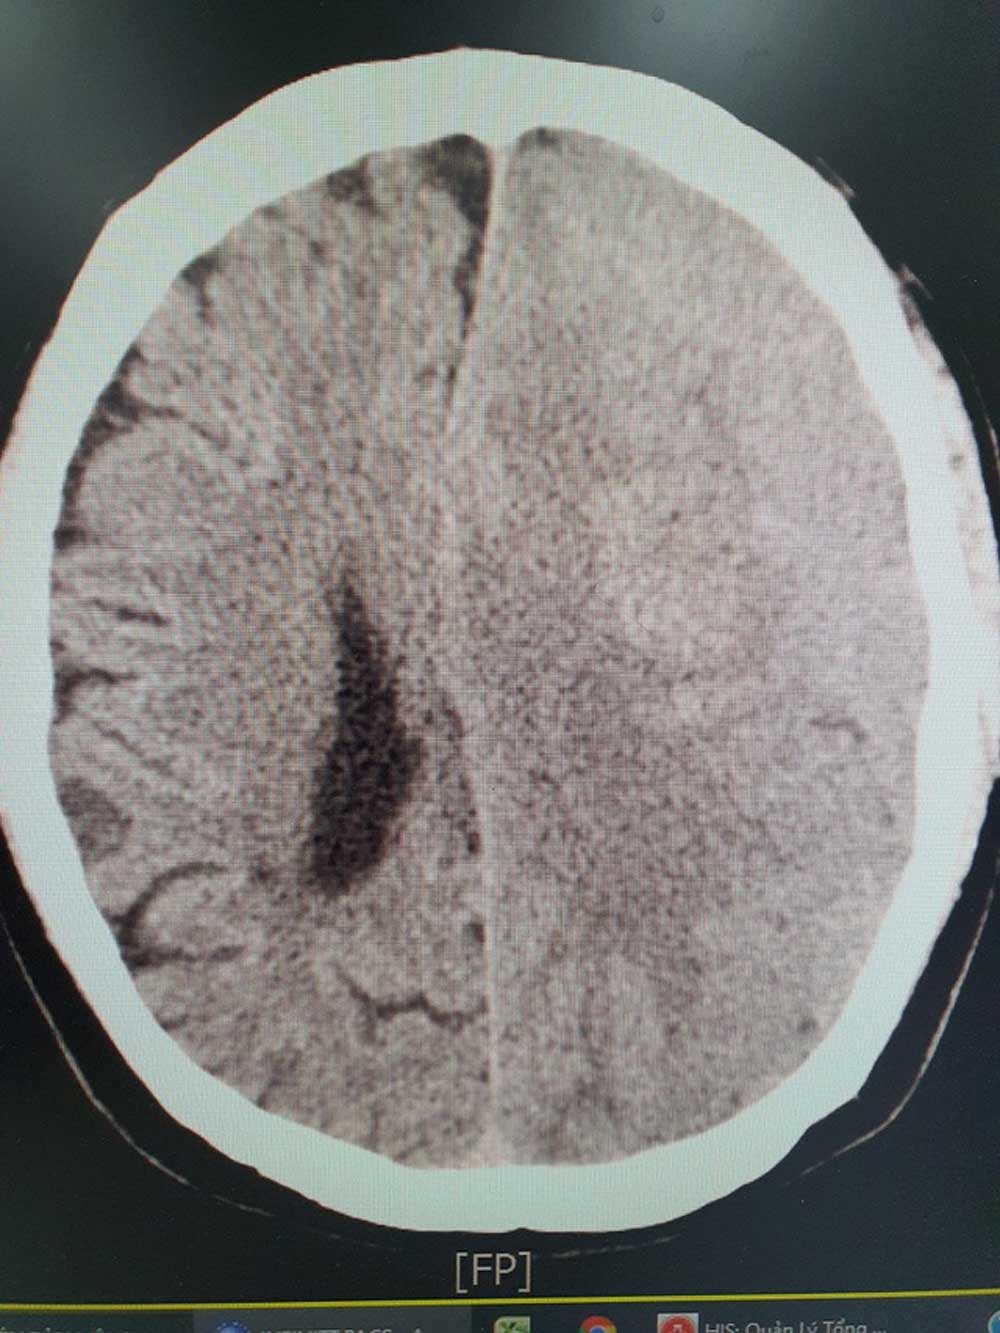

BS Khiêm cho biết, khi tiếp nhận bệnh nhân, các bác sĩ đã nhanh chóng chỉ định chụp cắt lớp CT và phát hiện bệnh nhân bị xuất huyết não có cục máu tụ dưới màng cứng. Ngay lập tức, bệnh nhân được tiến hành xử lý lấy máu tụ và sức khoẻ ổn định sau 4 ngày can thiệp.

![]() |

|

Khối xuất huyết não của bệnh nhân trên hình ảnh chụp CT. |